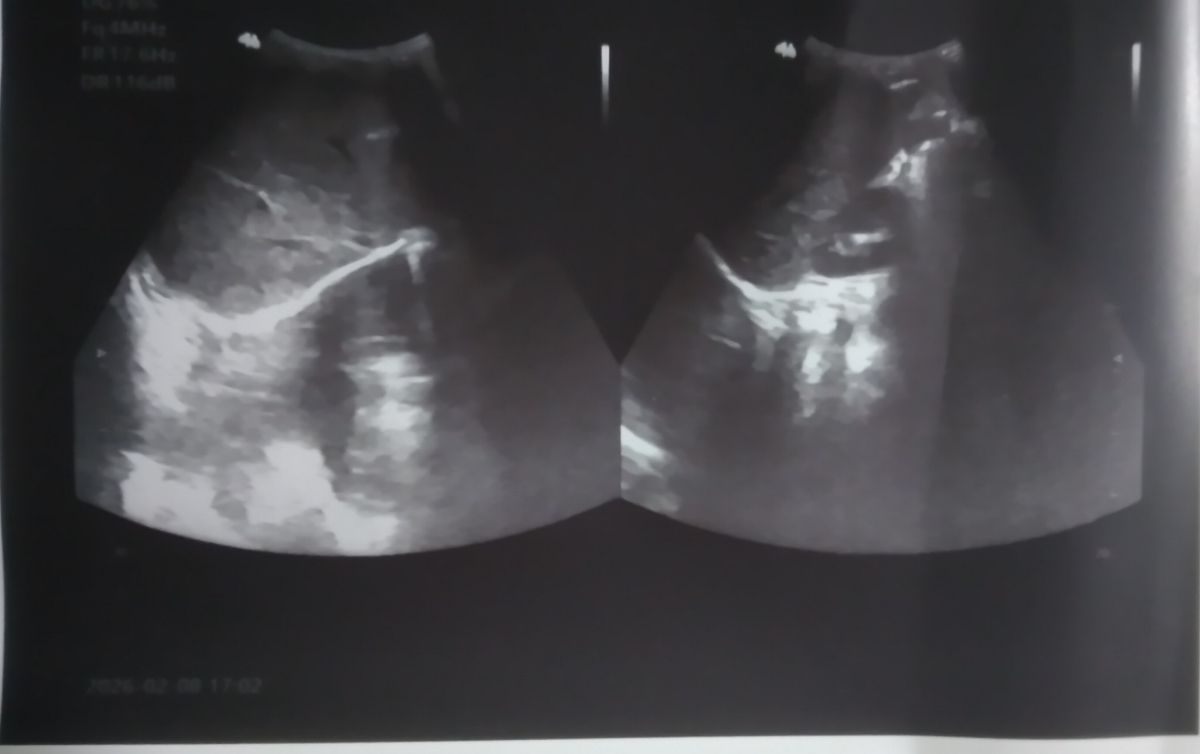

سلام دکتر عزیز وقتتون بخیر، میشه سونوی پسرمو یه نگاه بندازین دکتر سونو گفت سنگ داره ولی گفت خطرناک نیس به نظر شما با خوردن مایعات بیشتر دفع میشه یا حتما نیاز به دارو هست؟کلا چه موادغذایی براش خوبه چه موادی براش ضرر داره در حال حاضر؟

نه مشکلات ادراری نداره ولی یه مدت شبا به خودش میپیچید نمیتونست از درد بخوابه ما فکر میکردیم معده یا داخل شکمش یه مشکلی هست که دکتر براش سونو نوشت فهمیدیم سنگ داره

عزیزم آزمایش ادرار داده؟ آب خیلیخیلی بدهید نوشیدنی گازدار و خوراکی های خیلی شور و نمکی ندهید

درمورد دارو باید متخصص کلیه و مجاری ادراری اطفال تصمیم گیری کند

لبنیات بستگی به نوع سنگ دارد برای همین گفتم اگر آزمایش ادرار بدهبد شاید براساس نوع کریستال البته اگر دفع کریستال داشته باشد بتوان مقداری به نتیجه رسید

ممنون دکتر جان ،جواب کریستال آزمایش ادرارش منفی بوده توی این آزمایشی که براتون فرستادم

بله جانم دیدم ولی برای 5 ماه قبل بوده اگر آن زمان این مشکلات را داشته تکرار لازم نیست